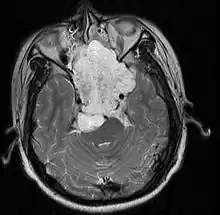

- Skull base:

- May be intracranial or extracranial, with mass effect symptoms depending on location

- Headaches and/or facial pain are common

- Pituitary insufficiency, hemianopsia/diplopia, cranial nerve deficits, nasal stuffiness.

Skull Base

- Hannover; 2007 (Germany) PMID 17695386 -- "Chordomas of the skull base: surgical management and outcome." (Samii A, J Neurosurg. 2007 Aug;107(2):319-24.)

- Retrospective. 49 patients. Transethmoidal approach 36%, pterional 23%, retrosigmoid 23%.

- Outcome: GTR 49%, subtotal resection 51%. Initial surgery GTR 78%. 5-year OS 65%, 10-year OS 39%

- Toxicity: New neurological deficit 12%

- Conclusion: Chordoma cannot be regarded as surgically curable tumors, given the 5- and 10-year OS